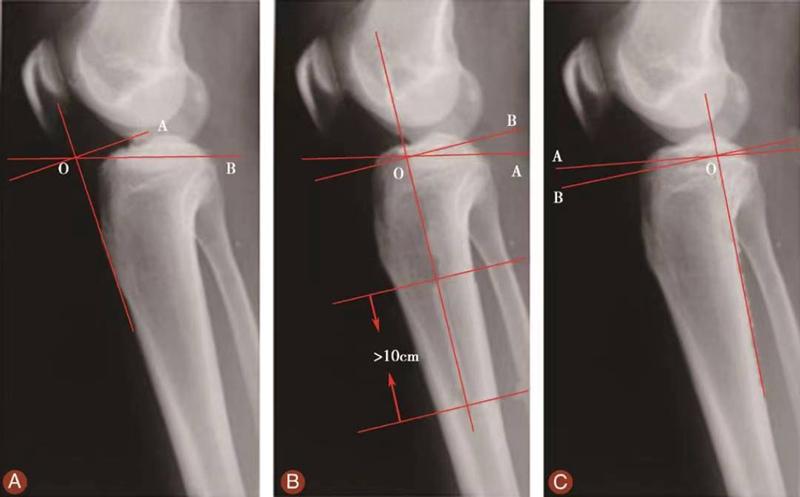

03、胫骨后倾角的评估

测量胫骨后倾角时先要观察胫骨上段及其与腓骨的位置关系,选择无明显胫骨旋转的,胫骨平台轮廓清晰的膝关节X侧位片。方法1测得的胫骨后倾角范围是11.74°±3.87°,方法2测得的胫骨后倾角范围是8.91°±3.57°,方法3测得的胫骨后倾角范围是6.21°±3.51°。

图15 胫骨后倾角的评估

用量角器测量胫骨内侧平台前后缘连线分别与胫骨中上段前侧骨皮质切线的垂线(图15A)、胫骨结节下胫骨中上段轴线的垂线(图15B)以及胫骨后侧皮质切线的垂线(图15C)的夹角,即胫骨后倾角(∠AOB)。